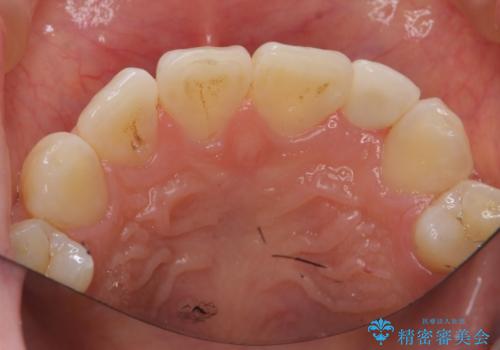

- 左上の前歯が生まれつき小さく、前に飛び出していました。

矯正治療で引っ込めてから、形を左右対称に整えるセラミック治療を行いました。

矯正治療と併用することで、劇的に見た目を改善することができます!